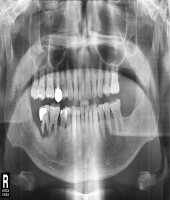

| ● 진료과목 : [임플란트] 치주환자의 보철치료

| ● 내용 : 60대 치주환자의 보철치료 |